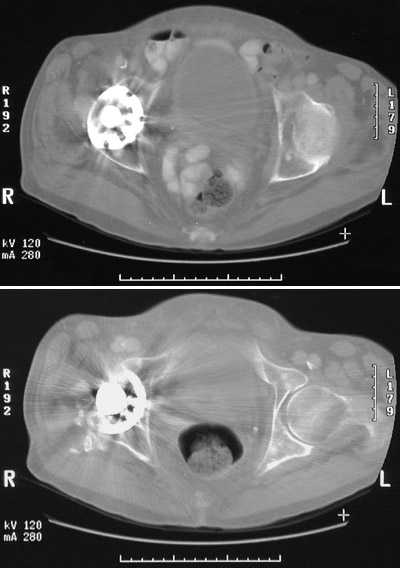

| Following a femoral fracture, a right hip prosthesis has been placed here. This is the appearance on CT scan, with attenuation reduced. Even so, the radiodense metallic prosthesis scatters the x-rays, obscuring other structures. Compare the normal hip joint on the left. |